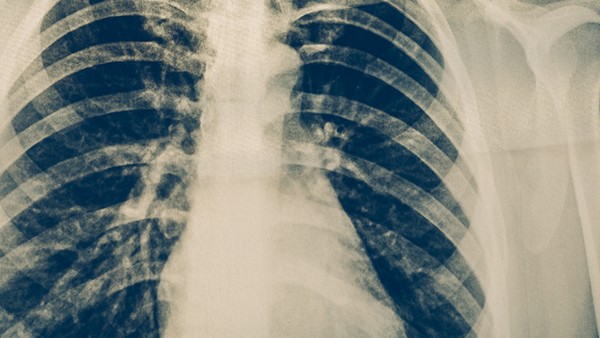

在进行PPD皮肤试验时,会在前臂内侧注射少量结核菌素,并且需要观察48~72小时左右的时间,在此期间如果局部出现了红肿或者硬结的情况,则属于阳性反应,说明身体感染了结核杆菌。如果没有其他不适症状,一般是正常的生理现象,不需要特殊治疗。